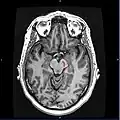

|  Section through superior colliculus showing substantia nigra. | |

Horizontal MRI (T1 weighted) slice with highlighting indicating location of the substantia nigra. Horizontal MRI (T1 weighted) slice with highlighting indicating location of the substantia nigra.